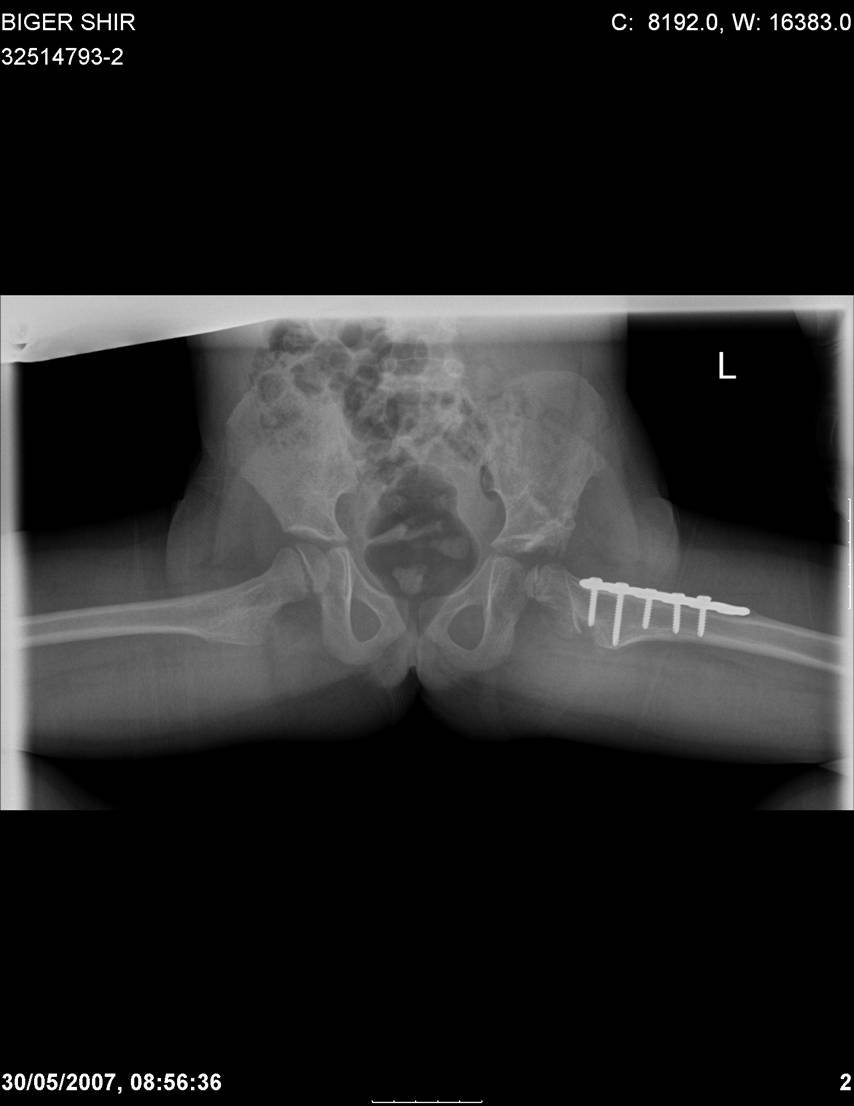

[Ortho] Врожденный вывих бедра

Navernoe Dega

Chto by ne byt goloslovnym posilau vam svoi sluchai gde sdelal vse chto napisal vyshe